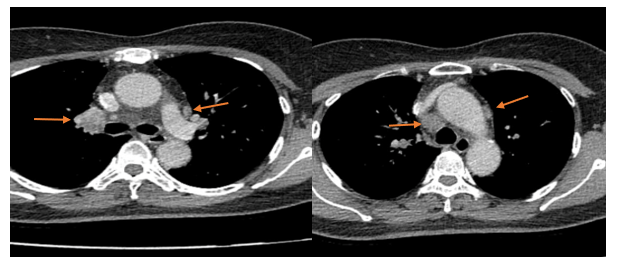

– Chụp cắt lớp vi tính lồng ngực: Nhu mô thùy trên phổi (Phải) có nốt tổn thương kích thước 13x14mm, bờ không đều, ngấm thuốc, sau tiêm. Rải rác nốt đặc 2 bên thùy phổi kích thước 3-10mm. Trung thất các nhóm 1R; 2R; 4R; 5; 8; 10RL có vài hạch lớn nhất kích thước 26x15mm; bờ không đều; ngấm thuốc không đồng nhất sau tiêm. Thượng đòn 2 bên có vài hạch tính chất tương tự; hạch bên phải kích thước 11x14mm

Hình 3: Hình ảnh cắt lớp vi tính ngực có tiêm: Trung thất các nhóm 1R; 2R; 4R; 5; 8; 10RL có vài hạch lớn nhất kích thước 26x15mm; bờ không đều; ngấm thuốc không đồng nhất sau tiêm (mũi tên màu cam)